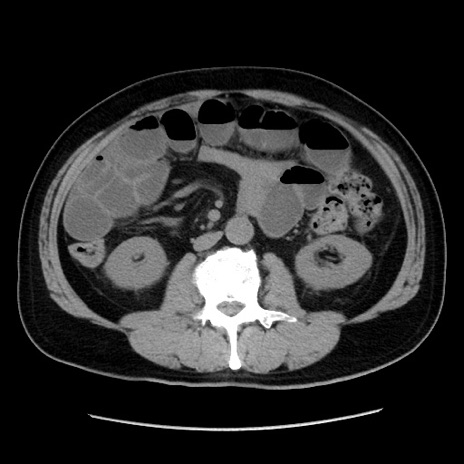

症例16(横断像)

【症例】 70歳代男性

【主訴】 腹痛、嘔吐

【現病歴】 約1ヶ月前より間欠的に腹痛と嘔吐あり、当院消化器内科を受診したところCTで多発する肝臓のLDAを指摘され、精査中であった。以降は消化器症状は安定していたが、2日前より嘔気と腹痛があり、同日より排便・排ガスが消失した。改善認めず、 本日、救急外来を受診した。

【既往歴】 大腸ポリープ切除後。

【身体所見】意識清明・会話良好、BT 36.3℃、BP 127/80mmHg、 P 80bpm、腹部:膨満あり、平坦・軟、上腹部正中および下腹部正中に圧痛あり、反跳痛なし、筋性防御なし。

【データ】WBC 7200、CRP 0.77